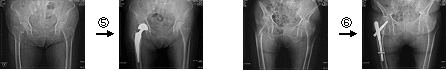

*大腿骨頸部骨折手術

当院では、高齢者の大腿骨頸部骨折に対し、人工骨頭置換術・観血的骨接合術などの手術を実施しています。手術時間も1時間~1.5時間と短く患者さんへの負担を軽減しています。また、入院中にはリハビリテーション病棟にて積極的に機能回復訓練をおこない早期の日常生活復帰を支援しております。